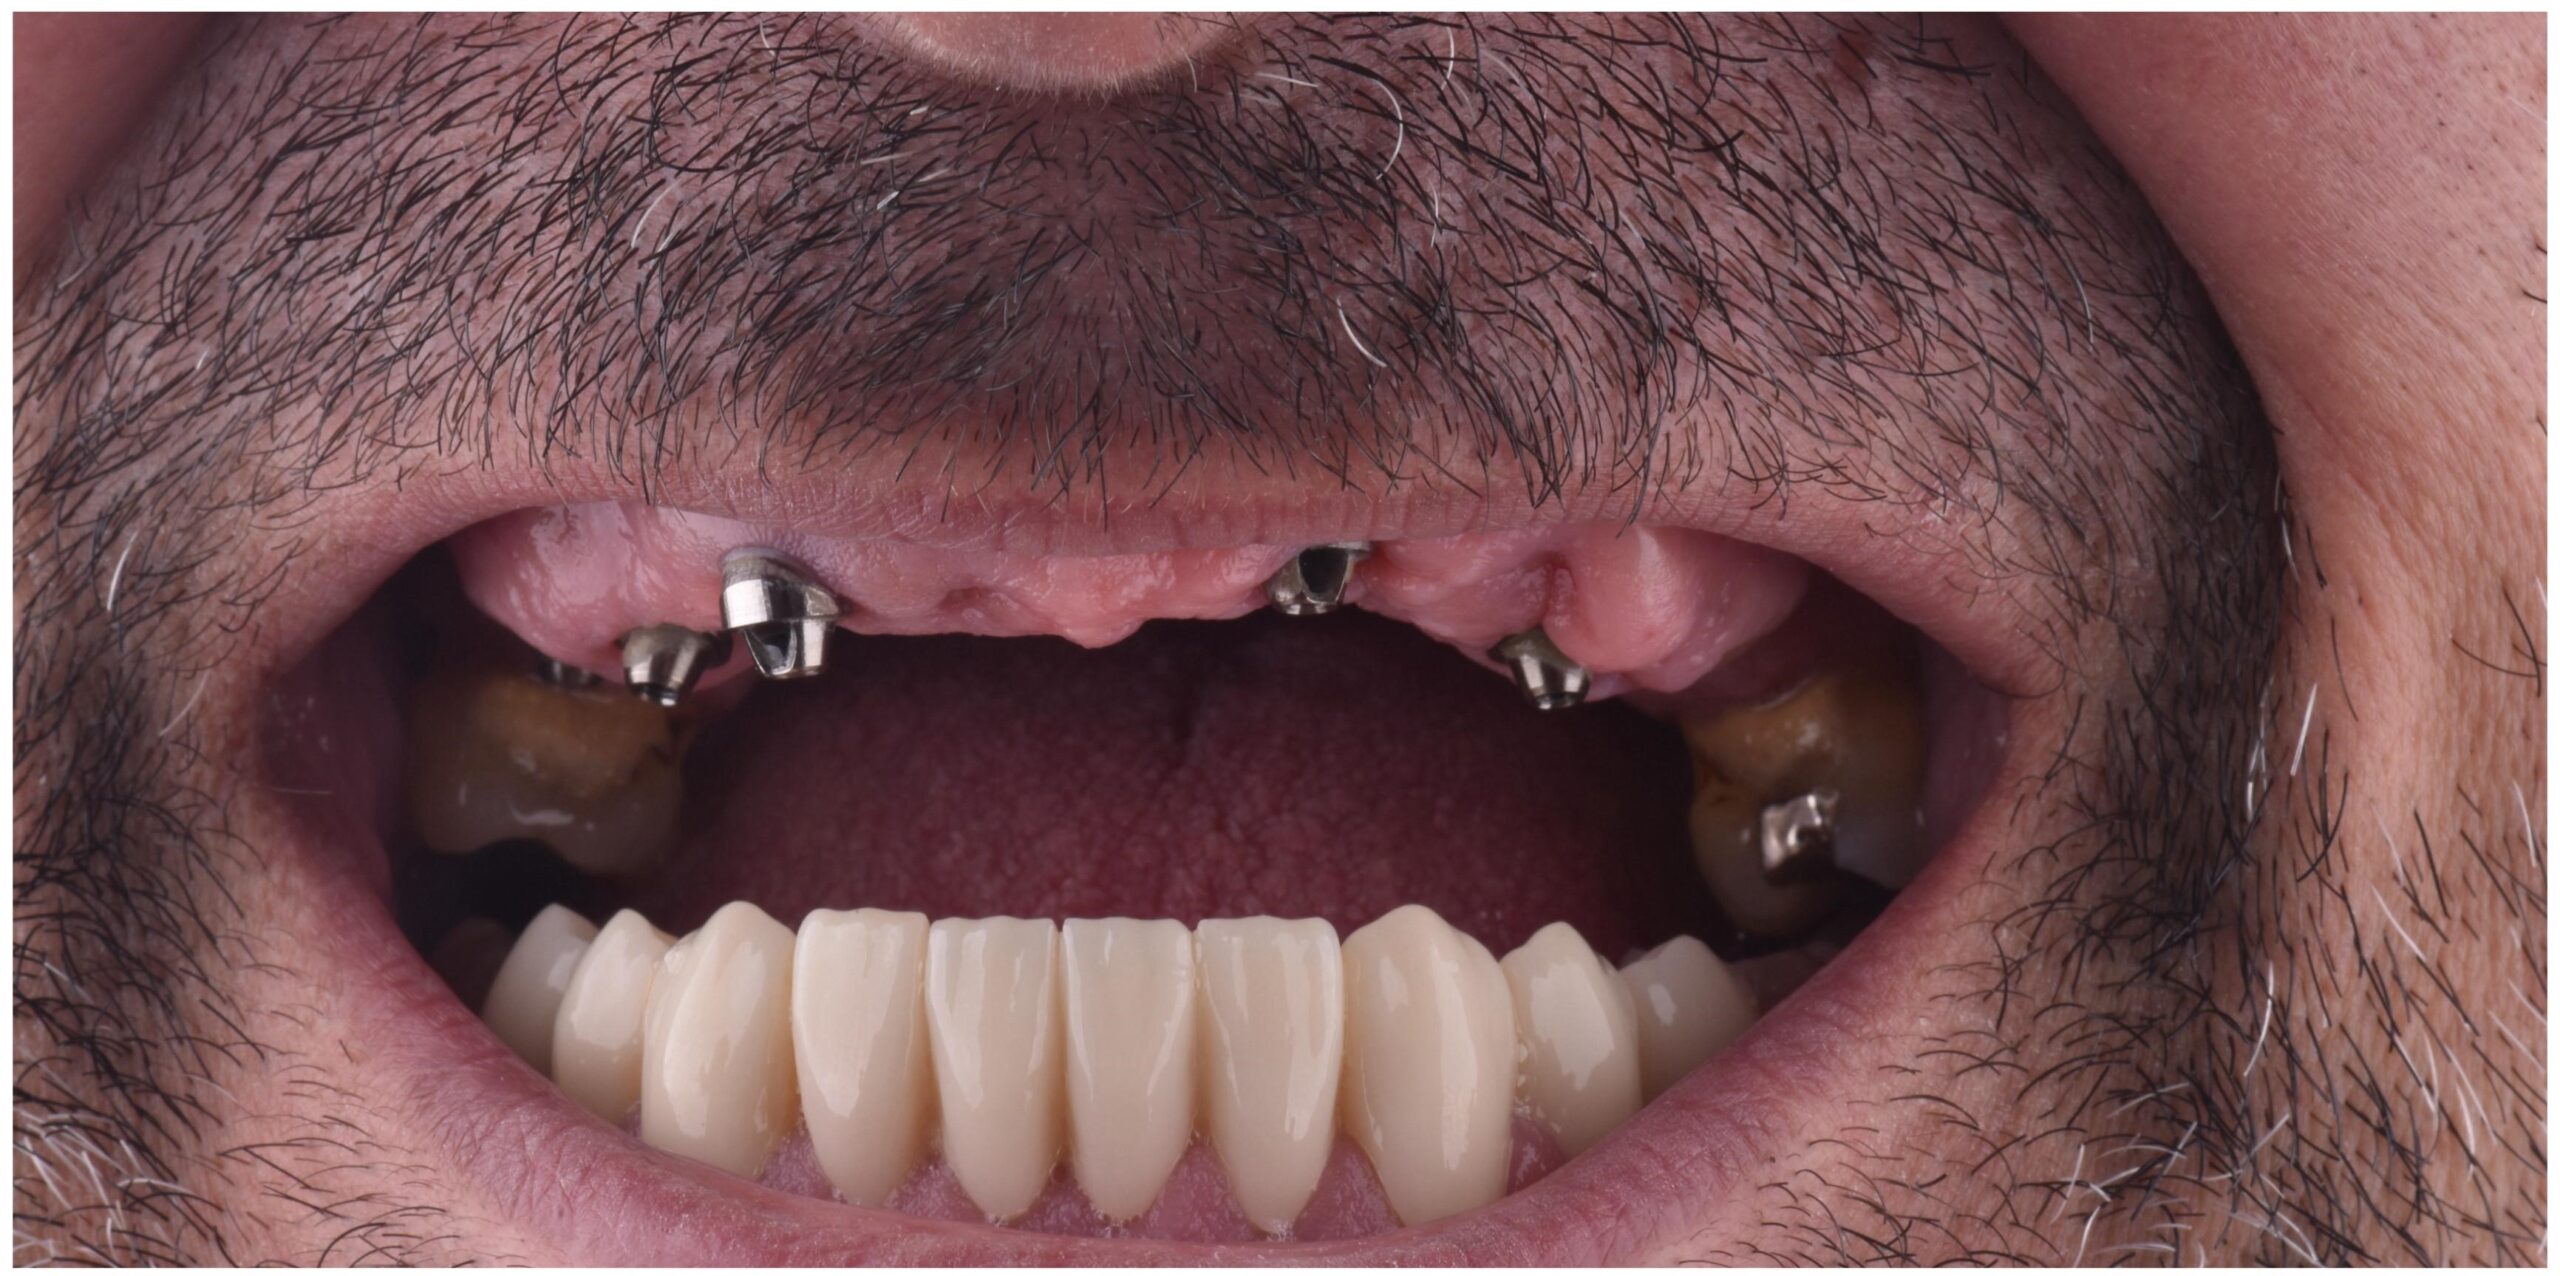

Our Work